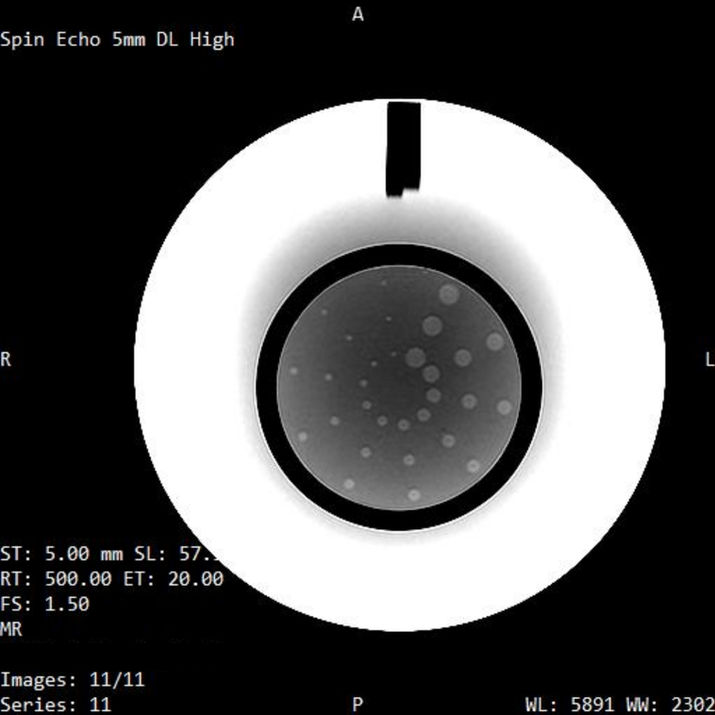

MR Phantom Test

Explore our collection of MRI phantom images, each annotated to highlight key assessment areas for MRI performance and image quality.

Series are acquired using the ACR Large Phantom and the NIST Premium System Phantom.

Analysis is conducted using advanced automated quantitative analysis software.